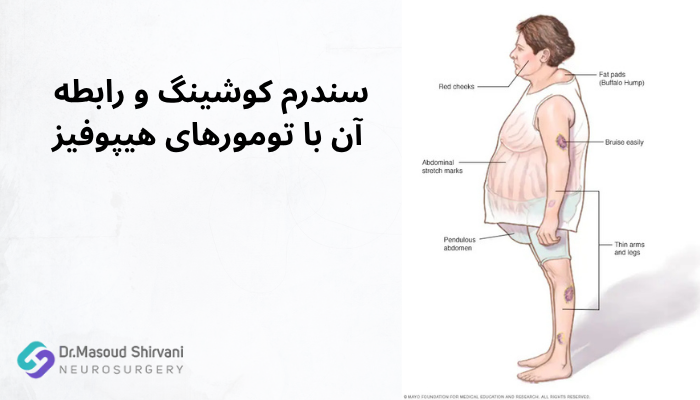

سندرم کوشینگ و رابطه آن با تومورهای هیپوفیز

سندرم کوشینگ زمانی رخ میدهد که سطح هورمون کورتیزول در بدن بیش از حد بالا باشد. یکی از دلایل اصلی آن، تومورهای هیپوفیز ترشحکنندهی ACTH هستند که باعث تحریک غده فوق کلیه و افزایش تولید کورتیزول میشوند.

افزایش مداوم کورتیزول، تعادل متابولیسم بدن را بر هم میزند و موجب چاقی مرکزی، تجمع چربی در شکم و صورت، ضعف عضلانی و افزایش قند خون میشود. این تغییرات معمولاً تدریجی هستند و در ابتدا ممکن است با اضافه وزن ساده اشتباه گرفته شوند.

درمان این وضعیت با کنترل یا برداشتن تومور، معمولاً باعث کاهش تدریجی کورتیزول و بازگشت وزن و وضعیت جسمی به حالت طبیعی میشود. به همین دلیل، تشخیص زودهنگام رابطهی میان تومور هیپوفیز و سندرم کوشینگ نقش مهمی در پیشگیری از عوارض بلندمدت دارد.